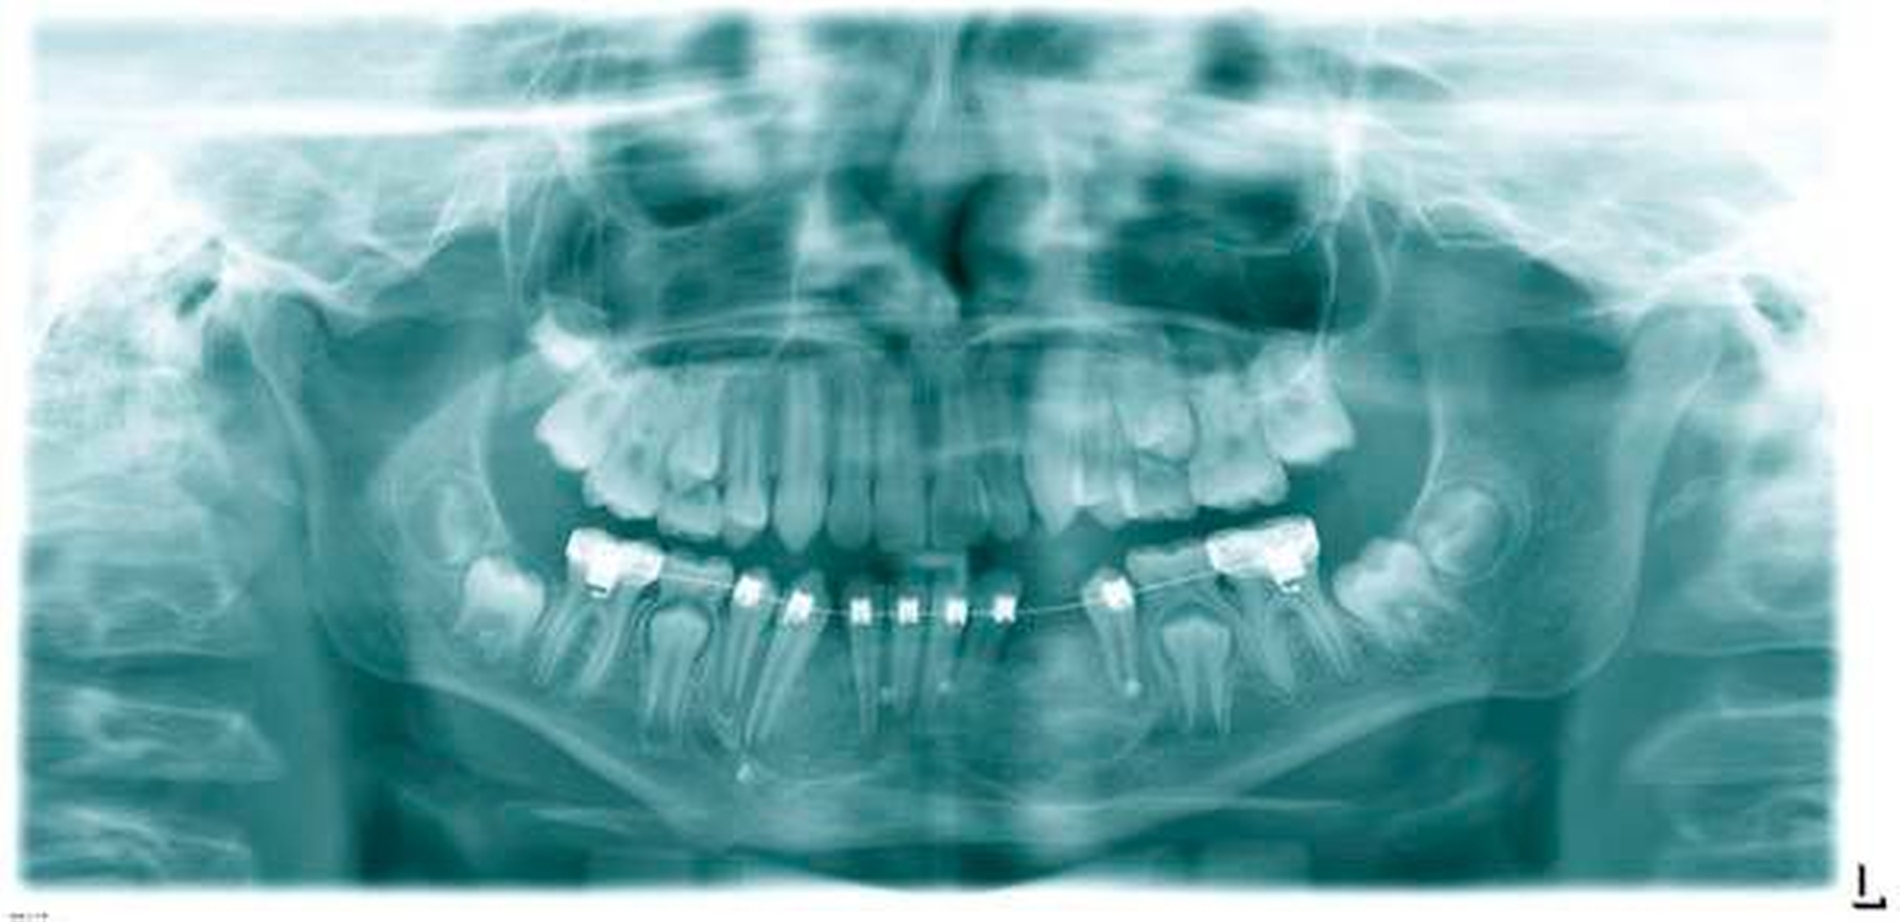

Ein zwölfjähriger Junge wurde in unsererKlinik zur Abklärung zweier unklarer, scharf begrenzter Raumforderungen der anterioren Mandibula vorgestellt. Diese fielen als Zufallsbefund im Rahmen eines Orthopantomogramms auf, das vom zuweisenden Kieferorthopäden angefertigt wurde. Aus der Allgemeinanamnese des Patienten ergaben sich keine Hinweise auf einen ursächlichen Zusammenhang.

Radiologischer Befund

Im OPG (Abbildung 1) sowie in der DVT (Abbildungen 2 bis 5) imponieren zwei scharf begrenzte osteolytische Befunde im Bereich der anterioren Mandibula regio 34–32 und 41–43. Der retinierte Zahn 33 liegt basal im Lumen der Aufhellung.